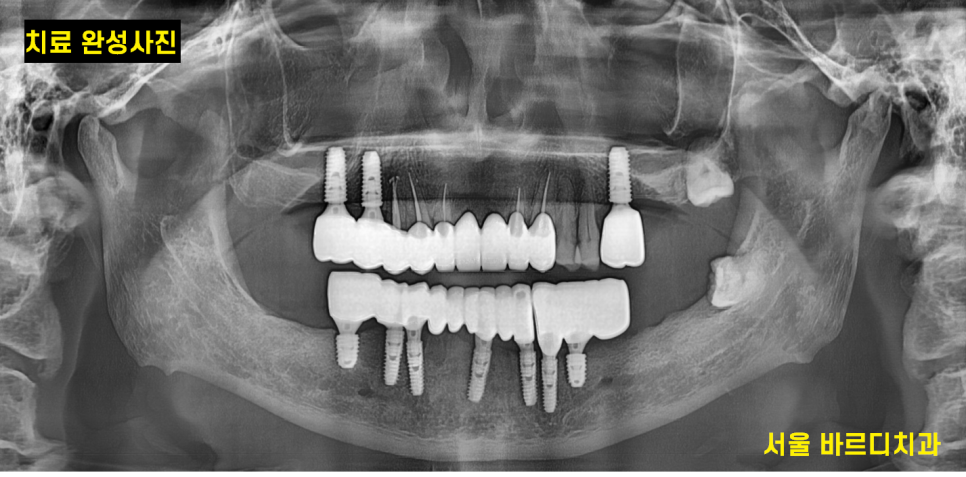

치료 후 사진입니다.

하악 전체 임플란트 7개로 12개의 머리를 완성

상악도 3개의 임플란트 치료를 진행했습니다.

약 5개월정도 치료 기간이 걸렸습니다.